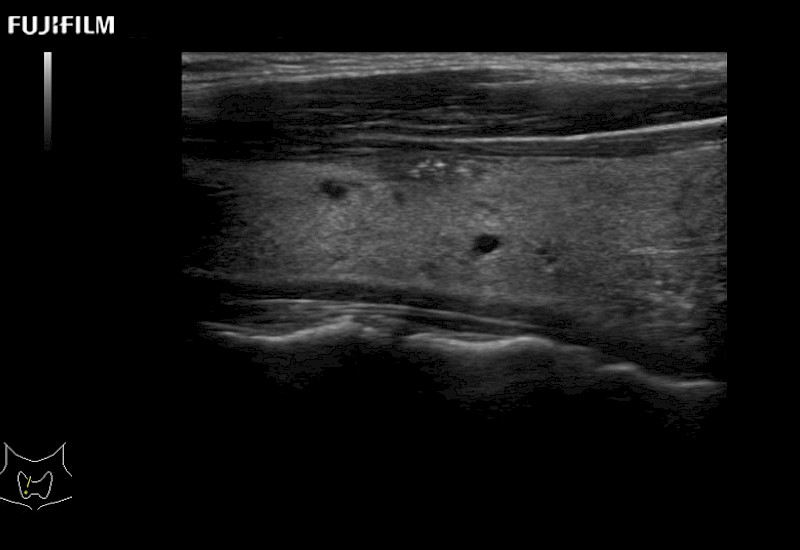

Learn moreFujifilm Healthcare continues to listen to the experts, our neurosurgeons, by developing an ultrasound system specifically designed for the Operating Room.

Guidance is the fundamental purpose for all of our surgical ultrasound technology. Fujifilm Healthcare is committed to designing tools that help neurosurgeons navigate inside the human body and provide the necessary information to immediately make critical surgical decisions.

With the ARIETTA Precision the next level of surgical ultrasound is here.